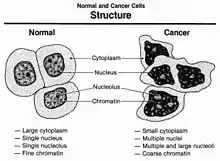

Cancer cells have distinguishing histological features visible under the microscope. The nucleus is often large and irregular, and the cytoplasm may also display abnormalities.[3]

Nucleus

The shape, size, protein composition, and texture of the nucleus are often altered in malignant cells. The nucleus may acquire grooves, folds or indentations, chromatin may aggregate or disperse, and the nucleolus can become enlarged. In normal cells, the nucleus is often round or solid in shape, but in cancer cells the outline is often irregular. Different combinations of abnormalities are characteristic of different cancer types, to the extent that nuclear appearance can be used as a marker in cancer diagnostics and staging.[4]